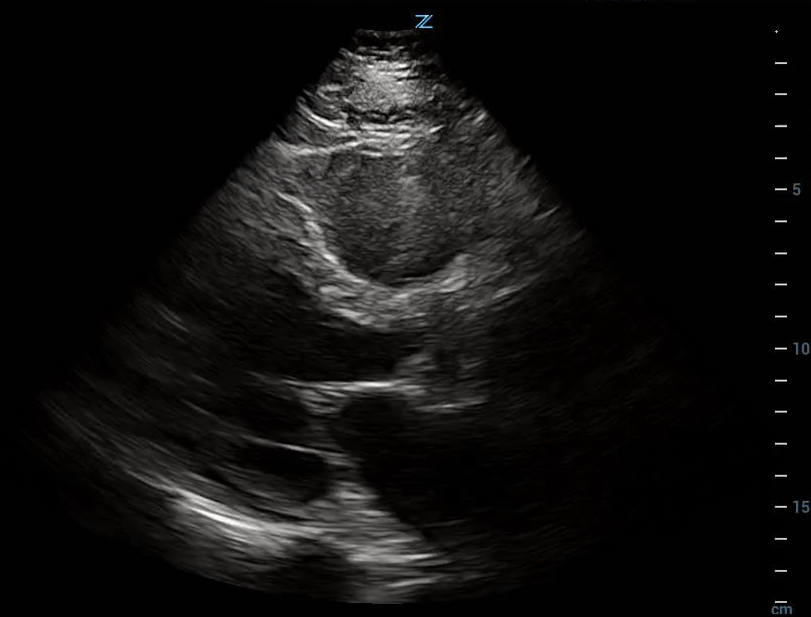

Severe Left Ventricular Dysfunction

Case 1:

LVEF 10%